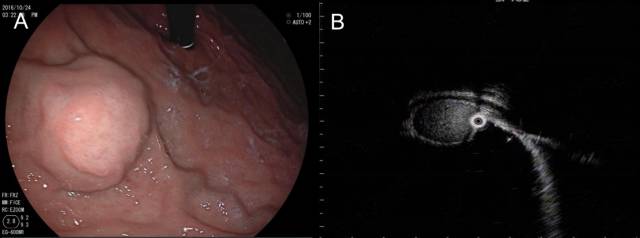

胃底肝左叶区域可见粘膜下半球形隆起,表面光滑(图 A),EUS见类圆形无回声病灶外压,其后方回声增强,可见囊性病灶特有的双侧折射声影(图B白箭头),故诊断为肝左叶囊肿外压。

2.肝血管瘤

不同于低回声的囊肿,血管瘤的超声影像通常为中、高回声病灶,上面病例就是一个肝左叶类圆形血管瘤外压导致的胃底隆起。CT等传统影像工具诊断肝脏病灶不难,但部分与胃壁关系密切的外生性血管瘤却是例外。